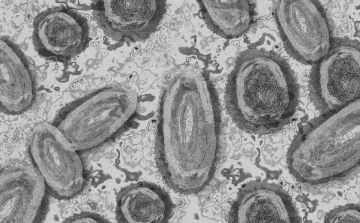

Megfertőződött a majomhimlővel egy gyerek Németországban

2022. Augusztus 10. 07:00, szerda | Külföld

Megfertőződött majomhimlővel egy négyéves kislány Németországban - jelentették kedden német hírportálok az országos közegészségügyi intézet (RKI) adatai alapján.